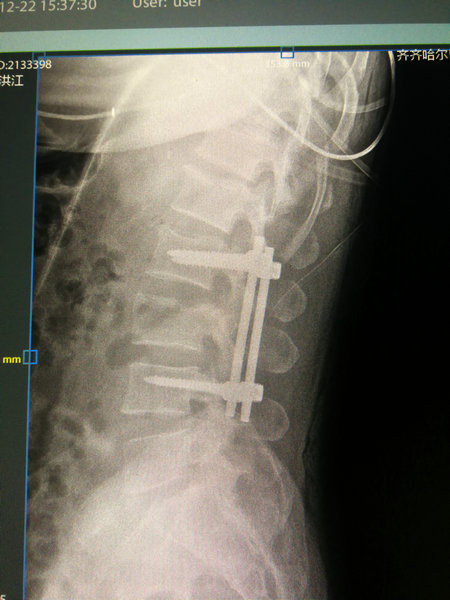

12月22日,一切准备就绪,陶先生如期进入手术室手术,在麻醉师的精准麻醉下,朱剑峰主任带领医疗团队按照既定手术方案历经1个半小时顺利完成了钉棒内固定术。

陶先生术后核磁影像

这个手术既能稳稳固定骨折的腰椎,同时对陶先生的创伤又降到了最低。术后第二天,陶先生的右下肢麻木感觉已有了明显缓解,双下肢肌力较术前也明显改善,这证明陶先生腰椎骨折已经得到了稳定固定,骨折对神经的压迫也得到了纠正。见到陶先生的病情迅速好转,病房的医护人员及家属都露出的欣慰笑容。